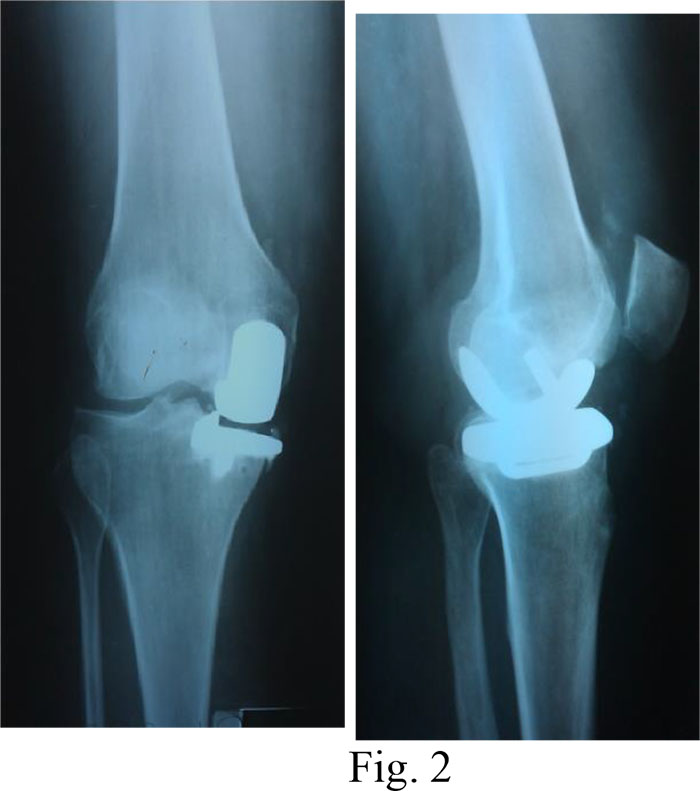

Diagnosis: III stage deforming arthritis of the left knee; varus deformity of the left knee; aseptic necrosis of the left femur’s medial process; pain syndrome.

Surgical treatment: a unicondylar arthroplasty of the left knee (Fig. 1a, b and 2)